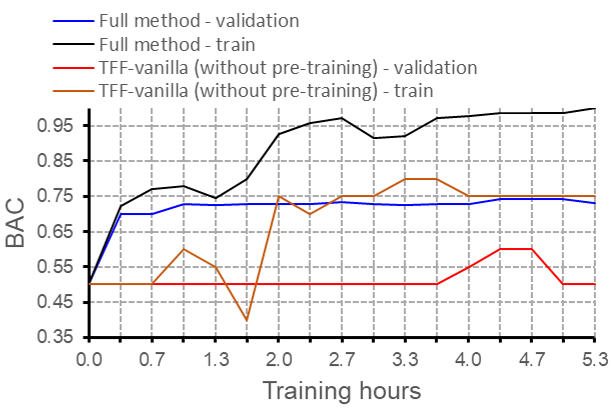

Comparing the convergence of TFF and TFF during the shared fine-tuning stage (appendix Fig. 8), it is evident that TFF struggles to converge, while the full model produces better results across the entire course of training. We attribute the enhanced performance of TFF to the effectiveness of the pre-training procedure. \textcolorblackAppendix F presents further empirical evidence in support of pre-training, in a different domain of MRI classification.

The results for comparing the convergence of TFF and TFF during the shared fine-tuning stage can be seen in Fig. 8. The results for the variable training set size experiment, from the main text, can be seen in Fig. 8.